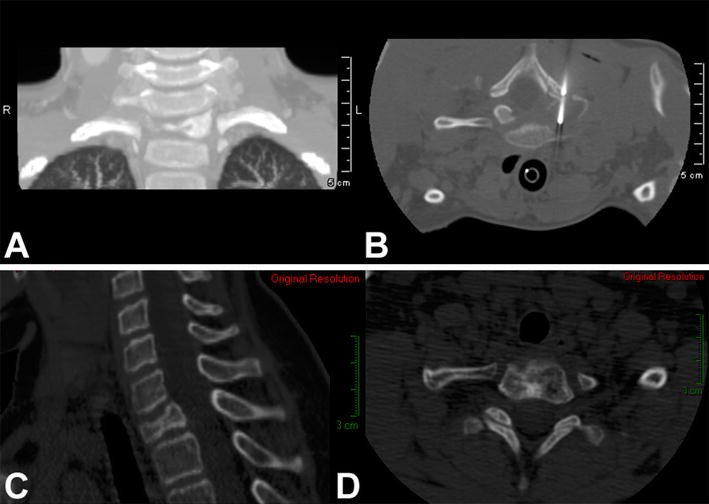

a Coronal CT scan of the cervical spine of a 5-year-old boy with a painful osteolytic lesion of the C7 vertebral body. b CT-guided frozen section biopsy showed eosinophilic granuloma; intralesional methylprednisolone injection was performed. c, d Sagittal (c)and axial (d) CT scans showing complete reconstitution of the lesion 5 years after diagnosis and treatment